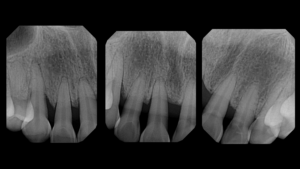

The matrix is removed from tooth #25, (Fig 24) and then #24 is injection molded. This to ensure a snug contact. The teeth are then rapidly sculpted together for sake of symmetry and efficiency. The final step is the Rock Star Polish. Invisible infinity edge margins are placed at mid-tooth. (Figs 25, 26) At one-year recall, the treated area is essentially bacteria and calculus-free, and the neighboring untreated embrasure is filled with calculus. The obvious health and quality of life of the treatment are a bonus to the esthetic benefits. (Fig 27) Pre- and post-operative radiographs demonstrate the imperceptible interface of composite to tooth and the void -free quality of the composite which is the goal if injection over-molded heated monolithic composite. (Figs 28, 29)